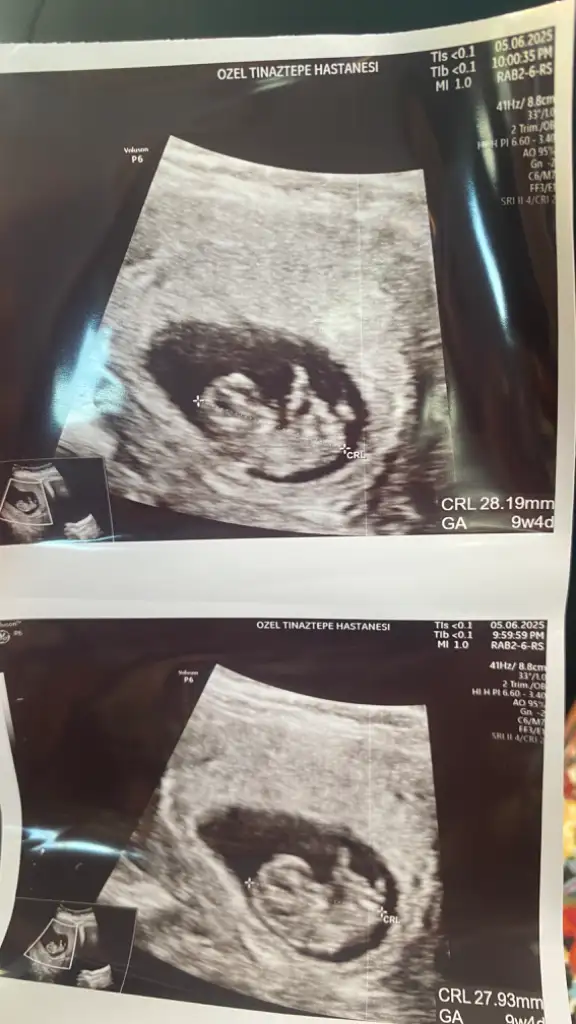

Cinsiyet tahmini

Bana da söyleyebilir misiniz acaba?

8+3 karından ultrasonla çekildi cinsiyet tahmini yapabilecek var mı acaba çok merak ediyorum